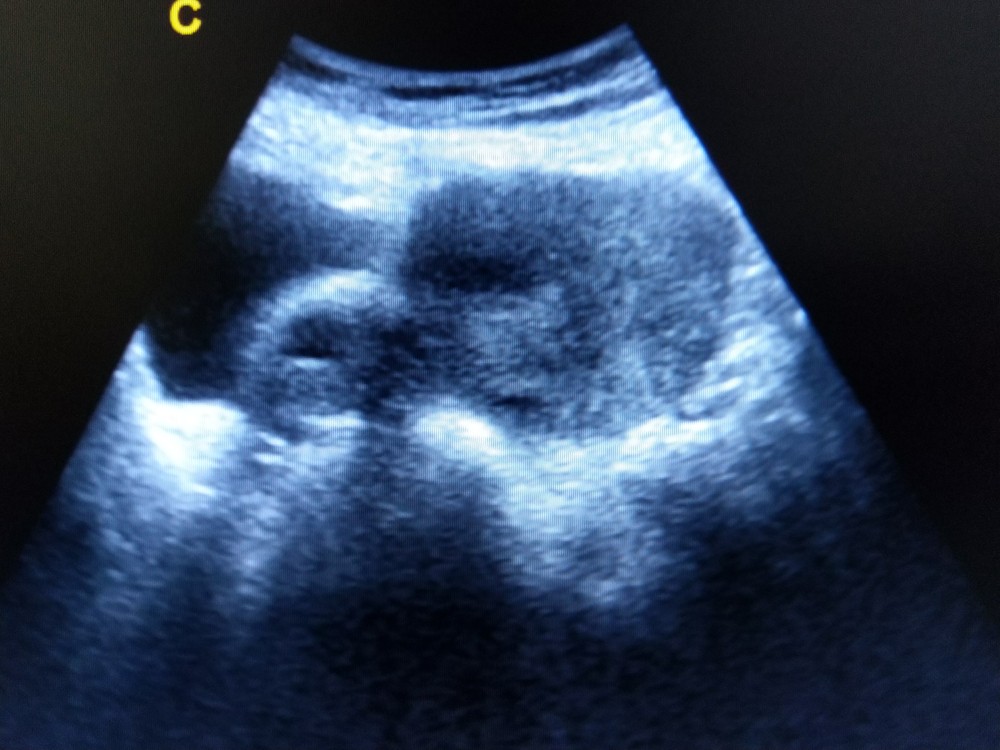

畸胎瘤在前期多數沒有症狀,通常都是在進行體檢或超聲波時被發現。有些會有尿頻、腹脹、輕度腹痛及壓痛感。當畸胎瘤發生扭轉時,會出現下腹絞痛、惡心、嘔吐等症狀,當出現這種情況時,需立即就診。

卵巢畸胎瘤一旦形成,靠打針、吃藥是無法消除的。畸胎瘤直徑小於3公分時,可定期進行超聲波追蹤檢查,若直徑大於3公分,需及早進行手術。畸胎瘤的手術類型有兩種,第一種是也是大多數的方法,就是手術切除腫瘤;第二種方法是移除卵巢。這兩種方式可采用傳統的開腹式或傷口較小的腹腔鏡手術治療。